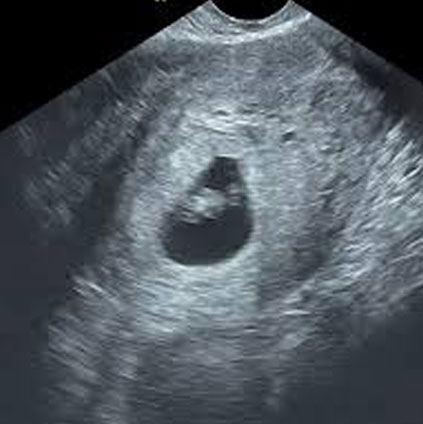

Ultrasound image showing nuchal translucency measurement during first trimester scan to detect chromosomal abnormalities in the fetus

An NT scan is a common screening test that is done during the first trimester of pregnancy i.e., between 11 – 14 weeks. This scan measures the size of the clear tissue, called the nuchal translucency (NT), at the back of the baby’s neck. It is a sonographic prenatal screening scan to detect chromosomal abnormalities in a fetus. The results of a nuchal translucency scan along with the blood tests and maternal age will tell if the fetus is at low, intermediate or high risk of a chromosomal abnormality.

The NT scan is performed usually transabdominally with a full bladder but occasionally the nuchal translucency can only be seen by transvaginal scan. It is often combined with a blood test, the double marker. The scan and the blood test together constitute the first trimester screening test.